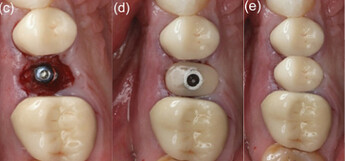

Minimally invasive removal of fractured premolar and placement of immediate implant (Megagen Anyridge) without osteotomy on Patient 3: (a) Fractured non‐restorable premolar. (b) Prepless immediate implant. (c) Cover screw placed to accommodate grafting with cortical cancellous allograft. (d) Anatomical healing abutment placed on the day of surgery. (e) Final monolithic Zr restoration. (f) Peri‐apical radiograph of day of surgery with anatomical healing abutment. (g) Peri‐apical radiograph with definitive restoration at 12 months.